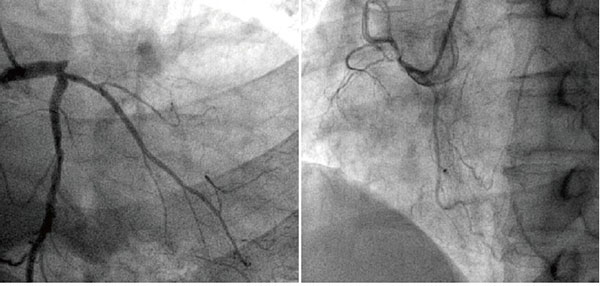

冠脈造影

冠狀動脈是給心臟供血的血管,當這個血管或者它的分支出現病變,我們就會患上冠心病(心肌缺血)。在輕度病變的時候, 患者沒有癥狀,或者出現心絞痛。嚴重病變的時候會有形成心肌梗死的風險。

前臨床常用的冠狀動脈造影檢查包括冠狀動脈CT血管造影(CTA)和介入冠狀動脈造影兩種,都是評價動脈是否存在病變以及指導治療的重要手段,兩者各有優缺點,也各有利弊,在不同情況下選擇不同的檢查方式,需要根據情況來決定,不能一成不變的認為CTA好或者介入造影更好。

冠脈造影檢測